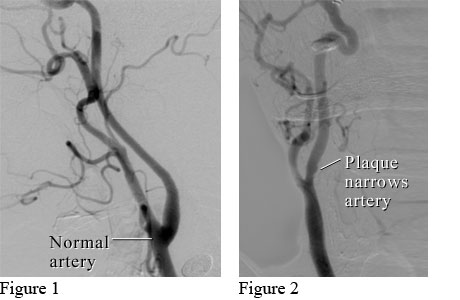

Angiograms of a normal neck artery and a neck artery narrowed by plaque

Figure 1 shows an angiogram (a type of X-ray) of a normal neck artery (carotid artery) with smooth walls. Figure 2 shows a carotid artery that is narrowed by a substance called plaque that builds up in the artery.